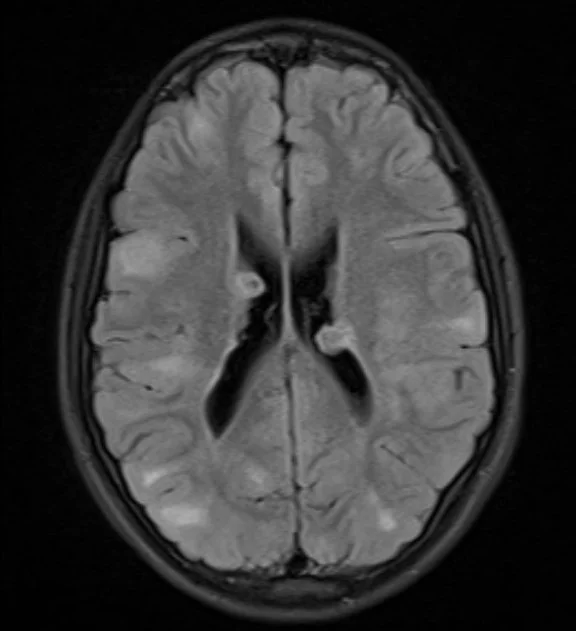

FLAIR:

• Showing obvious ventricular lesions which are iso-intense on T2 and FLAIR and demonstrate heterogeneous enhancement. This is a sub-ependymal hamartoma.

• Multiple hyper-intense subcortical (peripheral) lesions. These are cortical tubers.